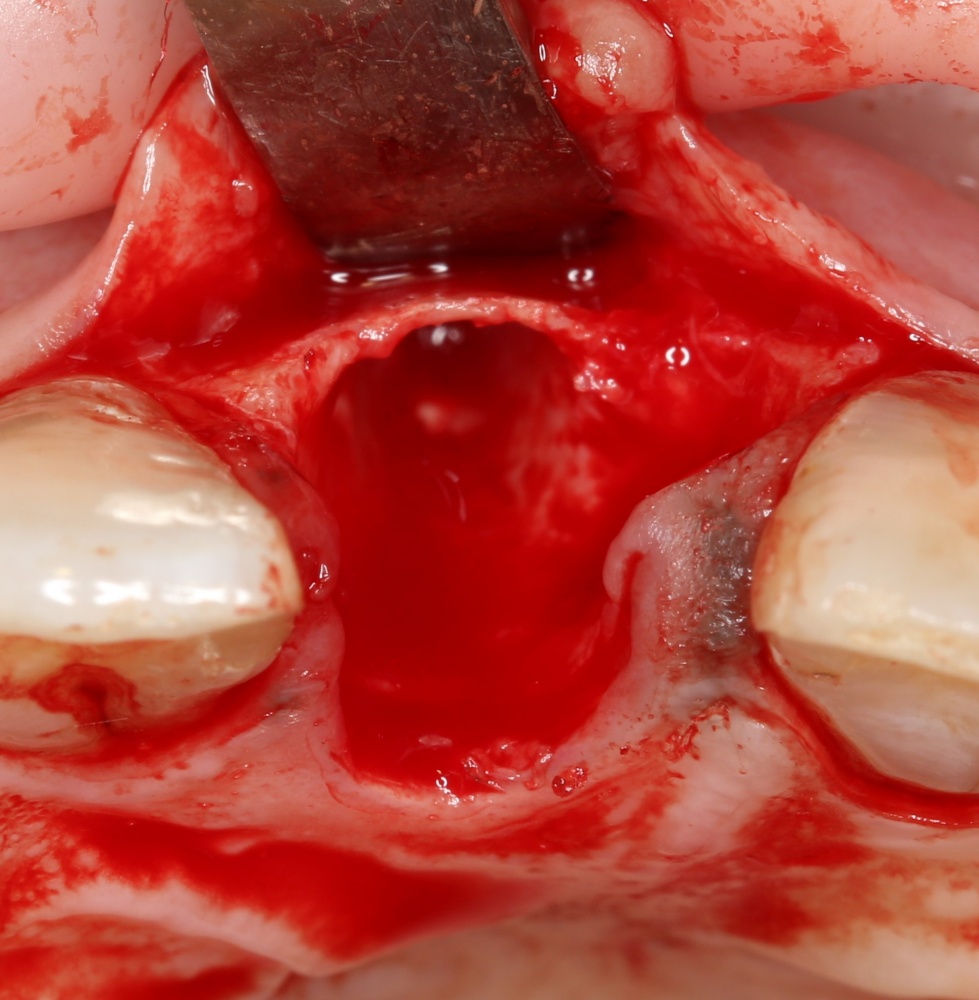

После удаления зуба и сопутствующей гранулемы, остается большая по размеру лунка с тонкой и поврежденной воспалительным процессом вестибулярной стенкой:

Первым делом, необходимо определиться с подготовкой лунки под имплантат. Проверить правильность позиционирования лунки можно с помощью аналогов имплантов, входящих в комплект XiVE Dentsply Implants:

Напомню, что при правильном позиционировании импланта в области фронтальных зубов, он прилегает к небной стенке лунки, а его ось выходит на небную поверхность будущей коронки. В крайнем случае, на режущий край.